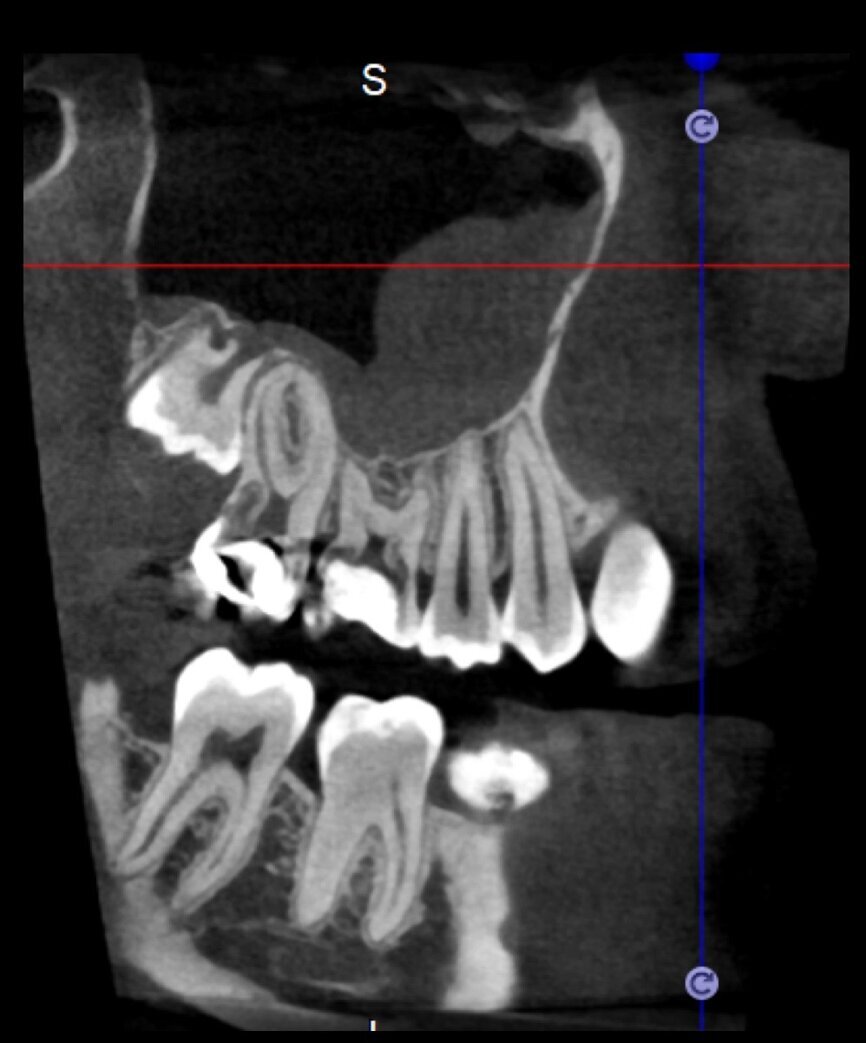

The case with which I would like to start my clinical review is a perfect example of how difficult it is to establish the origin of the patient’s symptoms on the basis of an intraoral radiograph alone. Not only does the 2D study fail to establish with certainty the presence of a lesion, but more importantly, it is impossible to establish the size, morphology and type of the lesion. An analysis of the 3D imaging, however, provides a clear picture of the clinical situation: the coronal and sagittal slices revealed the presence of a large lesion extending from the apex of the mesial root of this molar to the furcation, while the axial slices allow us to conduct a precise analysis of the endodontic anatomy and, in particular, the shape of the mesial root, which in this case was fused with the palatine root. A full overview of the case can, therefore, guide the decision-making process and direct the treatment plan towards a specific type of treatment (Figs. 1–4).